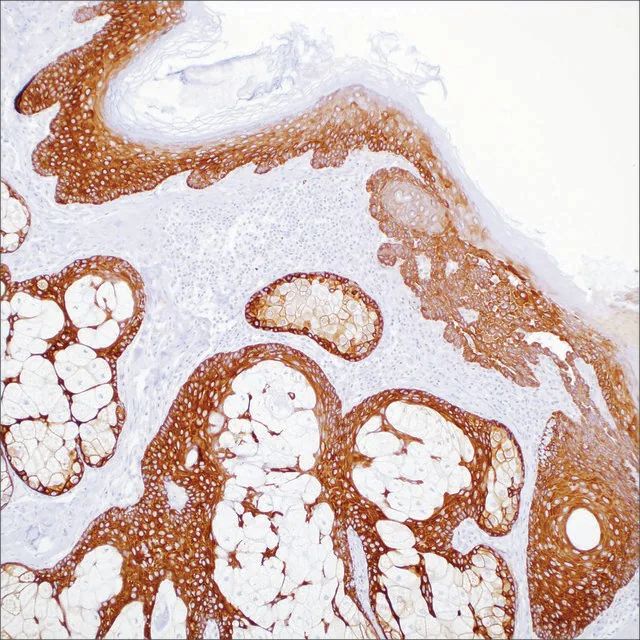

Blastic plasmacytoid dendritic cell neoplasm (BPDCN), previously known as CD4+/CD56+ hematodermic neoplasm or blastic NK-cell lymphoma, is a malignant neoplasm composed of immature hematopoietic precursors of plasmacytoid dendritic cells. The most frequent manifestation is a skin lesion, bone marrow involvement, and regional lymphadenopathy. Myeloid leukemia cutis (LC), myeloid sarcoma, and large aggressive B cell lymphomas should be differentiated from BPDCN. Recently, it has been reported that these entities can be distinguished by using immunohistochemistry (IHC) in paraffin-embedded tissue sections. In this study, 23 myeloid LC and 12 BPDCN cases were evaluated using a panel of antibodies against CD123, TCL1, CD4, CD56, MPO and CD33; with results as follows: anti-CD123 stained 4 cases (17%) of myeloid LC and 10 cases (83%) of BPDCN; anti-TCL-1 stained 2 cases (9%) of myeloid LC and 9 (82%) of 11 cases of BPDCN; anti-CD4 stained 2 cases (9%) of LC and all 12 cases (100%) of BPDCN; anti-CD56 stained 12 cases (52%) of LC and all 12 cases (100%) of BPDCN; anti-myeloperoxidase stained 7 cases (30%) of LC and 0 cases (0%) of BPDCN. Anti-CD33 was not helpful; it stained 18 (78%) cases of LC and 11 cases (92%) of BPDCN. The results indicated that a panel that includes antibodies against CD4, CD56, CD123, and TCL-1 can appropriately distinguish between myeloid LC and BPDCN.

CD123 Positive Control Slides, Product No. 198S, are available for immunohistochemistry (formalin-fixed, paraffin-embedded sections).

控制 blastic plasmacytoid dendritic cell neoplasm